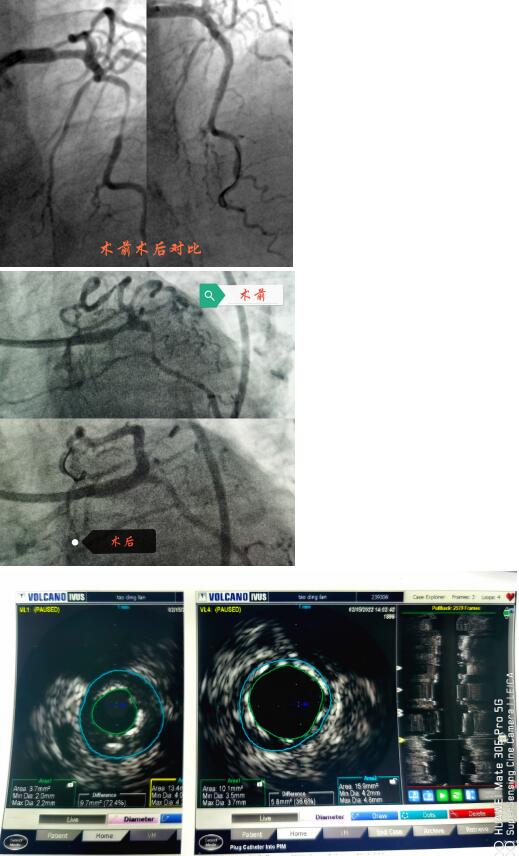

春節(jié)剛過,陶奶奶的孩子們帶著陶奶奶再次來到了江寧中醫(yī)院心內科準備拆除這顆潛在的“致命炸彈”。韋鋒主任反復研究陶奶奶的前期手術影像,心中擬定著多個手術方案。經過充分準備,2月15日,韋鋒主任再次為陶奶奶進行了介入手術。術中通過血管內超聲(IVUS)精細、準確評估陶奶奶的冠脈病變情況,發(fā)現(xiàn)陶奶奶的左主干最小管腔面積僅僅3.7mm2,;前降支近段全程鈣化,最嚴重處呈270度的環(huán)形鈣化,最小管腔面積僅僅2.1mm2;回旋支開口正常,回旋支近端最小管腔面積1.8mm2。韋鋒主任根據(jù)IVUS的結果,改變了原來擬定的DKCRUSH術式,決定采用藥物球囊和藥物涂層支架相結合的方式處理病變(LCX藥物球囊,LM-LAD植入支架),經過近2個小時的手術,陶奶奶的冠脈血管又“完美”地回來了。

韋鋒主任術中在仔細研究陶奶奶的IVUS結果,指導手術更精確的進行。

據(jù)韋鋒主任介紹,上世紀八十年代,類似陶奶奶的這種累及左主干的多支病變,曾被視為內科微創(chuàng)介入的禁忌,隨著心內科微創(chuàng)介入技術的發(fā)展和支架的更新?lián)Q代,目前,這類病變可以在有豐富介入經驗的介入醫(yī)生面前“迎刃而解”,不再是那么的可怕。近幾年隨著IVUS、OCT等腔內影像學的發(fā)展,這類病變可以更精準的進行治療。比如陶奶奶這個情況,在IVUS指導下,可以精確測量左主干的狹窄程度和長度,指導支架的選擇;準確評價左主干的解剖形態(tài)及病變性質,結合分叉處各分支開口的病變情況,制定更優(yōu)更個體化的介入治療策略,并且評價支架置入后的效果優(yōu)化支架置入的過程,整體改善患者遠期預后。